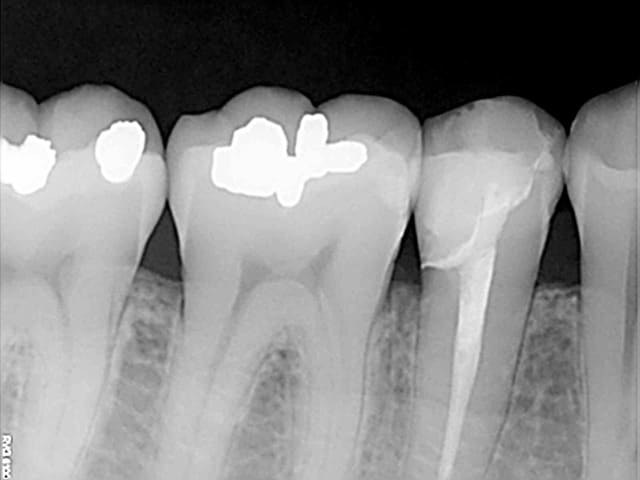

La radio montre un très fin hiatus en cervical au niveau du joint dent-inlay montrant probablement que l'inlay n'était probablement pas à fond à cause du contact trop fort.

> La radio montre un très fin hiatus en cervical au niveau du joint dent-inlay

> montrant probablement que l'inlay n'était probablement pas à fond à cause du

> contact trop fort.

Si tous les patients pouvaient avoir des restauration aussi adaptées on serait bien contents...